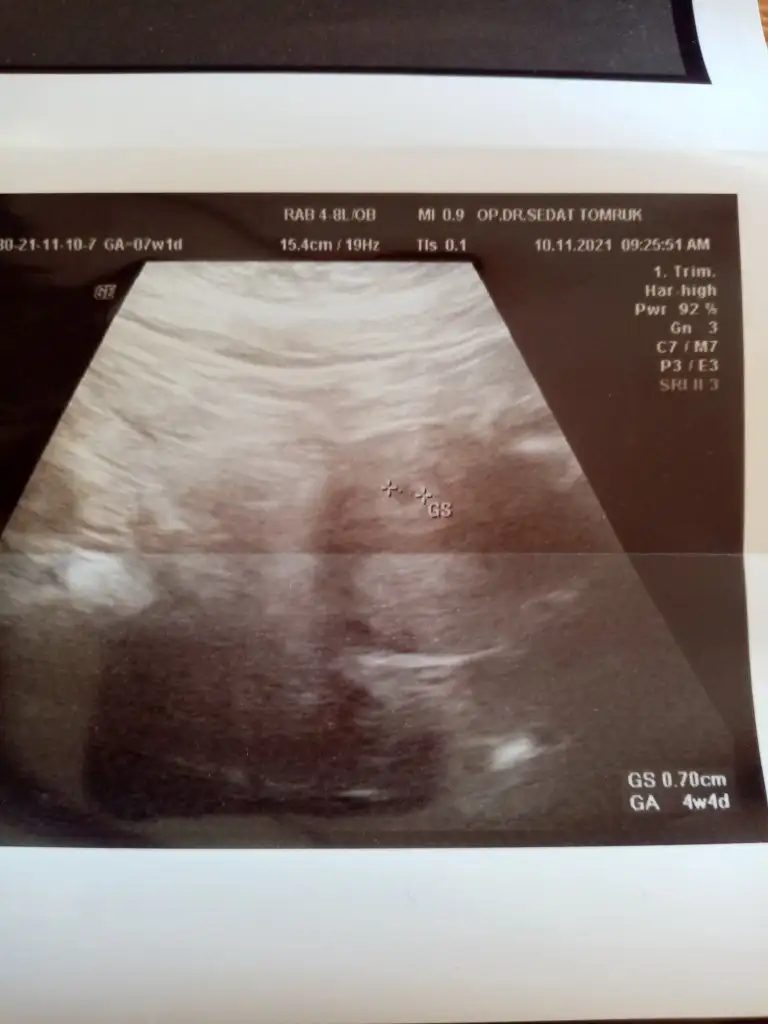

Canım kese haftaya göre değil beta değerlerine göre görünüyor. Mesela ilk gebeliğimde daha düşüktü değerlerim kese 5+2 de göründü. Ama bu seferki değerlerime göre yarın gitsem görebilir yani 4+5 deMerhaba, bu sabah adet geçikmem yüzünden ve hiç inancım olmadan sırf psikolojim rahatlasın diye test yaptım ve anında çift çizgi çıktı. Şoktayım ve 4+4 günlük hamileyim. Cuma günü doktora gitmeyi planlıyorum. Sizce kese gözükür mü?

Canımm gözünaydnBu sefer özelde bile bulamayacagım 4.4 luk bir dr geldm karnımdakıyle ilgilenmesı ayrı kucuk oglumla ilgilenmesi ayrı guzeldiortam yok ya ıysını buluyorum ya kotusunu bu arada kesecümüü gördüm rahtladım doktor kanama kist vb yok haftasıyla hatta günü gününe uyumlu kesen dedi ilerleyen haftalrda kan tahlili isteyecgni ona gore hareket edecegmzii soyledi simdilik hersey yolunda hamdolsun